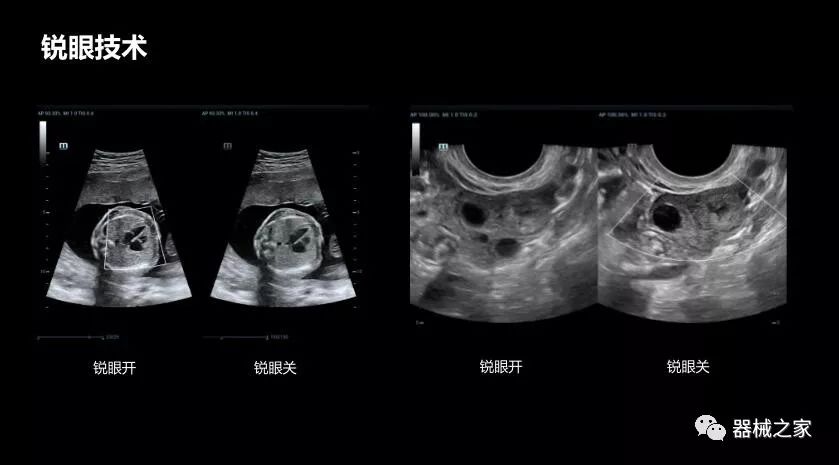

銳眼技術(shù)

做胎兒心臟檢查的時(shí)候,如果是聲窗不好的孕婦,很難看清胎兒心腔 。女?huà)zResona 8的銳眼技術(shù)能很好的優(yōu)化心腔內的噪聲,讓胎心結構完美的呈現。